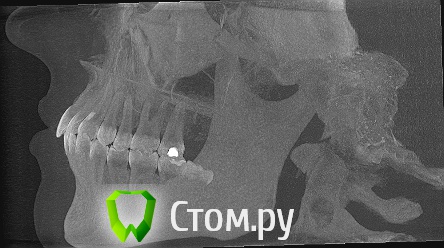

Дарья87 Опубликовано 13 мая, 2014 Автор Поделиться Опубликовано 13 мая, 2014 Еще есть снимки может кто то что то сможет прояснить.Возможно здесь есть хороший специалист.Нуждаюсь в совете.За раннее спасибо! Ссылка на комментарий

Дарья87 Опубликовано 13 мая, 2014 Автор Поделиться Опубликовано 13 мая, 2014 Восьмой зуб который на снимке его уже нет.Удалила так как он не мог выйти на поверхность и встать в зубной ряд Ссылка на комментарий